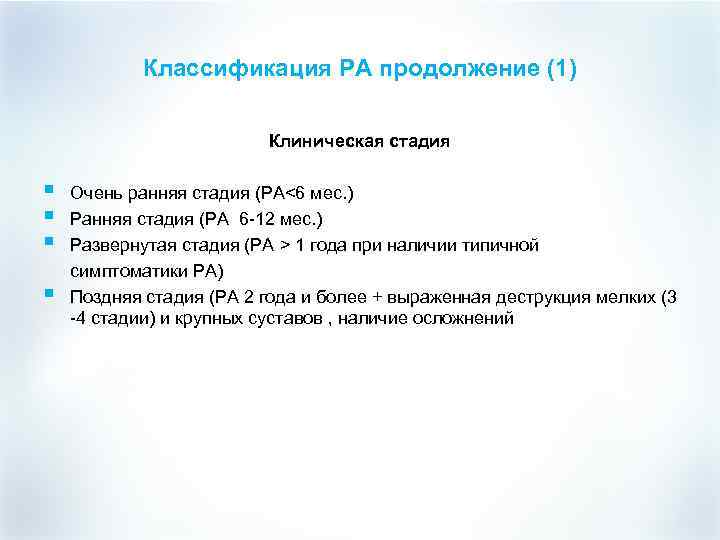

Классификация РА продолжение (1) Клиническая стадия § § Очень ранняя стадия (РА<6 мес. ) Ранняя стадия (РА 6 -12 мес. ) Развернутая стадия (РА > 1 года при наличии типичной симптоматики РА) Поздняя стадия (РА 2 года и более + выраженная деструкция мелких (3 -4 стадии) и крупных суставов , наличие осложнений

Классификация РА продолжение (1) Клиническая стадия § § Очень ранняя стадия (РА<6 мес. ) Ранняя стадия (РА 6 -12 мес. ) Развернутая стадия (РА > 1 года при наличии типичной симптоматики РА) Поздняя стадия (РА 2 года и более + выраженная деструкция мелких (3 -4 стадии) и крупных суставов , наличие осложнений